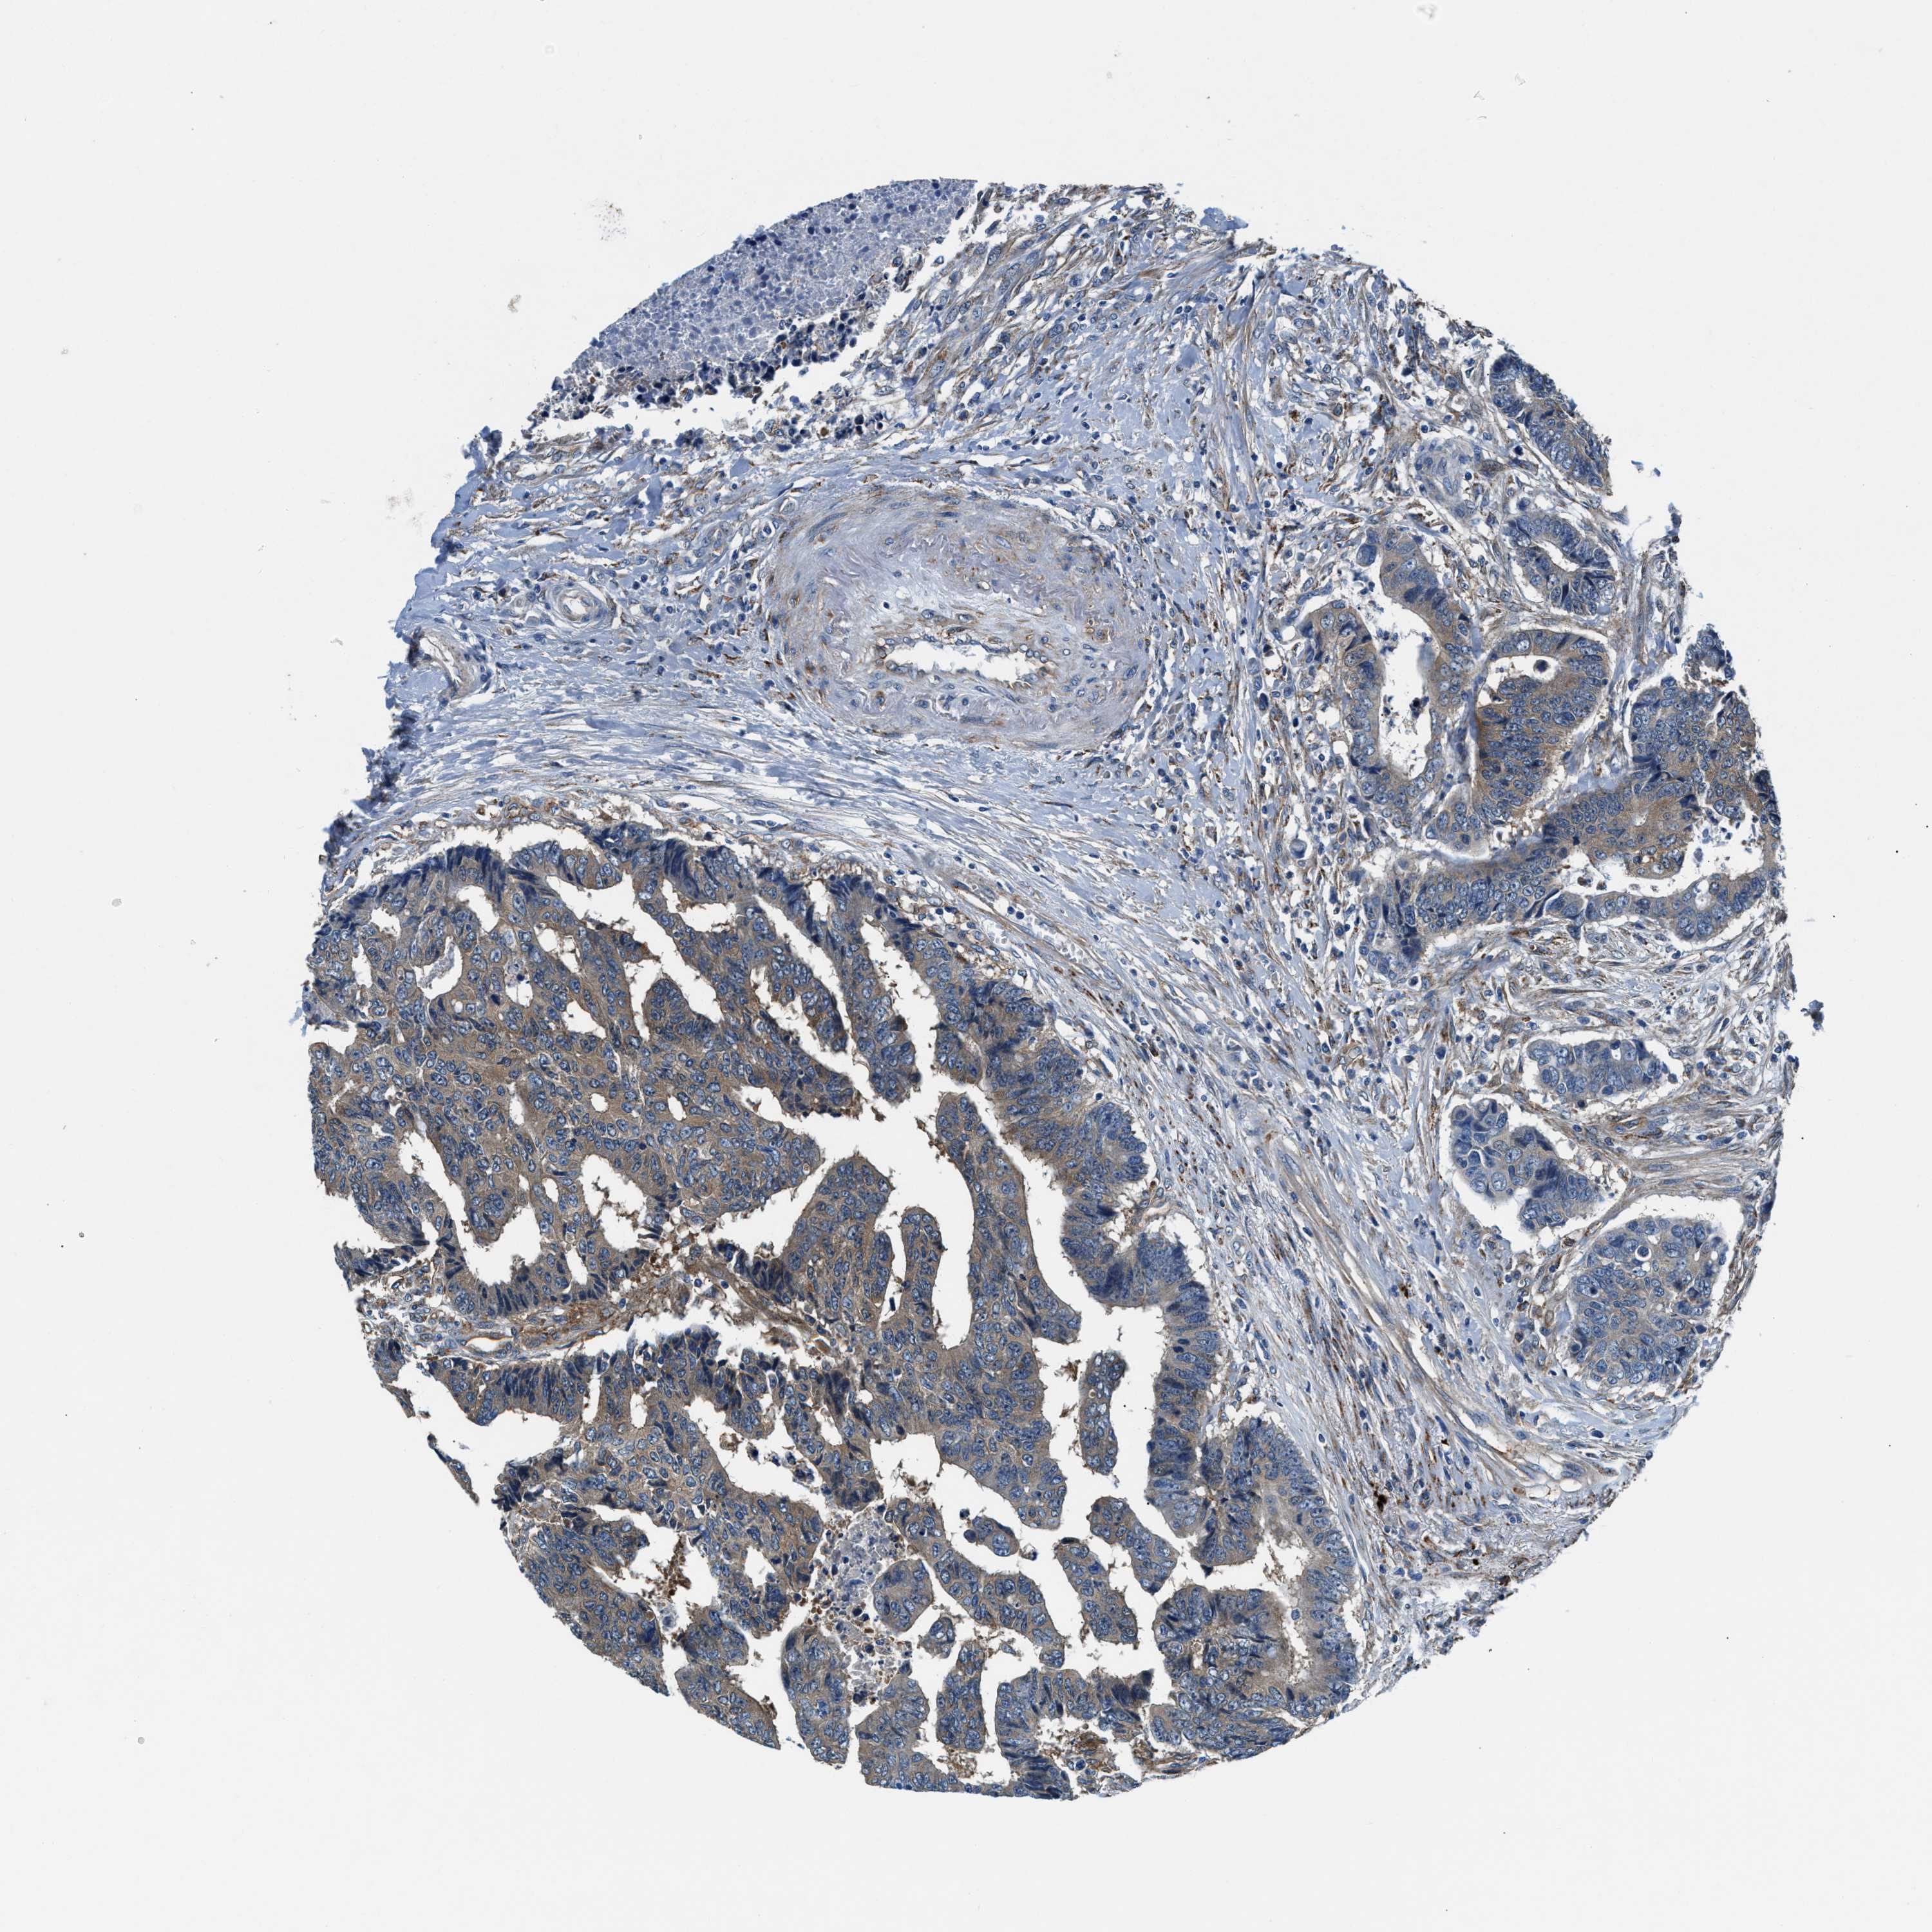

CANCER COLORECTAL CANCER Show tissue menu

Colorectal cancer

Human cancer

Colon adenocarcinoma

Rectum adenocarcinoma